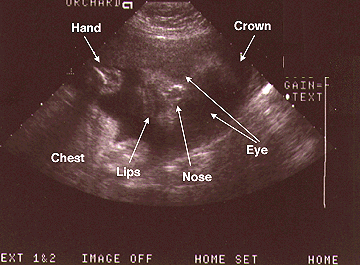

Week 30: March 2, 1998

O.K, we know! The first ultrasound photo was the money shot. There was little doubt - there they were in all their glory, Mister Pee Pee and his friends, Mister Testacles. Even I could tell what they were. It also has hands and feet. Here are our most recent photos.

After searching the world over for a place to have an ultrasound, I stumble on one in Port Orchard. It won't be as sophisicated as the one at Harrison, but who cares. At least we get to see what this Alien inside me looks like. Here's a better picture, face on. Tilt your head to the right and it'll match the angle of Parker's head.